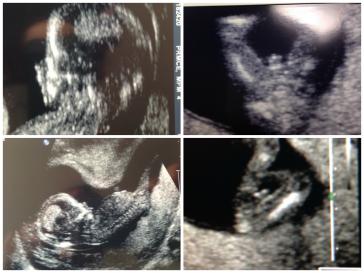

13w4dAttachment 17776

Yep, those are boy bits - they're not going to disappear. Congrats!